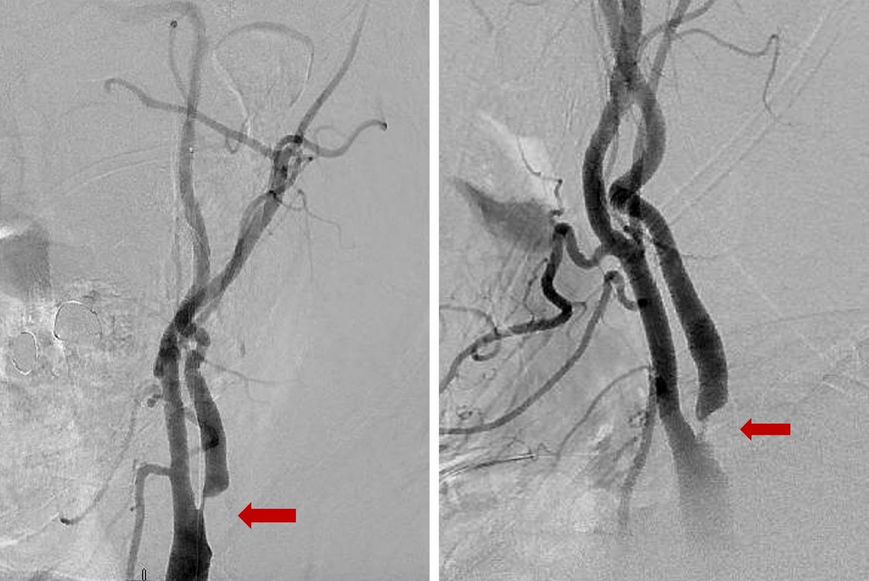

Carotid Stenosis is also called carotid disease is a narrowing of the Carotid Artery in your neck, which supplies blood to the brain. Carotid stenosis is most commonly caused by carotid atherosclerosis (buildup of plaque in the artery) or other conditions such as trauma or infection. As the narrowing increases, blood flow to the brain is reduced and blood clots can form leading to stroke. Read more…